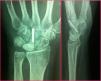

El rango de movimiento de la muñeca medio mejoró en todos los casos con respecto a los valores preoperatorios, registrándose unos valores prácticamente similares al de la muñeca contralateral en casi todos los casos (figs. 4 y 8), si bien en algún caso se observó en los primeros meses una limitación para la flexión palmar de la muñeca. Los datos de movilidad preoperatoria y postoperatoria se muestran en la tabla 1.

No se apreciaron modificaciones en el índice de Youm después de la cirugía, obteniéndose un valor medio de 0,47mm. Cuatro semilunares presentaban un tipo ii (fig. 1) y 2 un tipo iii según la clasificación morfológica de Antuña Zapico. Tampoco hubo cambios significativos en las mediciones radiológicas del semilunar antes y después de la cirugía. En todos los pacientes se consiguió la consolidación del foco de la osteotomía a los 3,5 meses de media (3-5 meses) y en ningún caso se constató una necrosis del polo proximal del HG.

En 4 de los pacientes revisados se realizó RM al año de evolución tras la cirugía, apreciándose en un caso la progresión de la EK de un estadio iiiA de Lichtman a un estadio iiiB, con agravamiento de la fragmentación del Se. No se detectaron aflojamientos del material de síntesis. No se encontraron diferencias reseñables en las RM realizadas en el estudio final actual con respecto a las anteriores.

En 2 de los casos, aparte de cambios posquirúrgicos, esclerosis y edema parcheado en semilunar, se apreciaron discretos signos de revascularización (fig. 7), si bien no encontramos en ningún caso signos de regresión o mejora del estadio inicial.